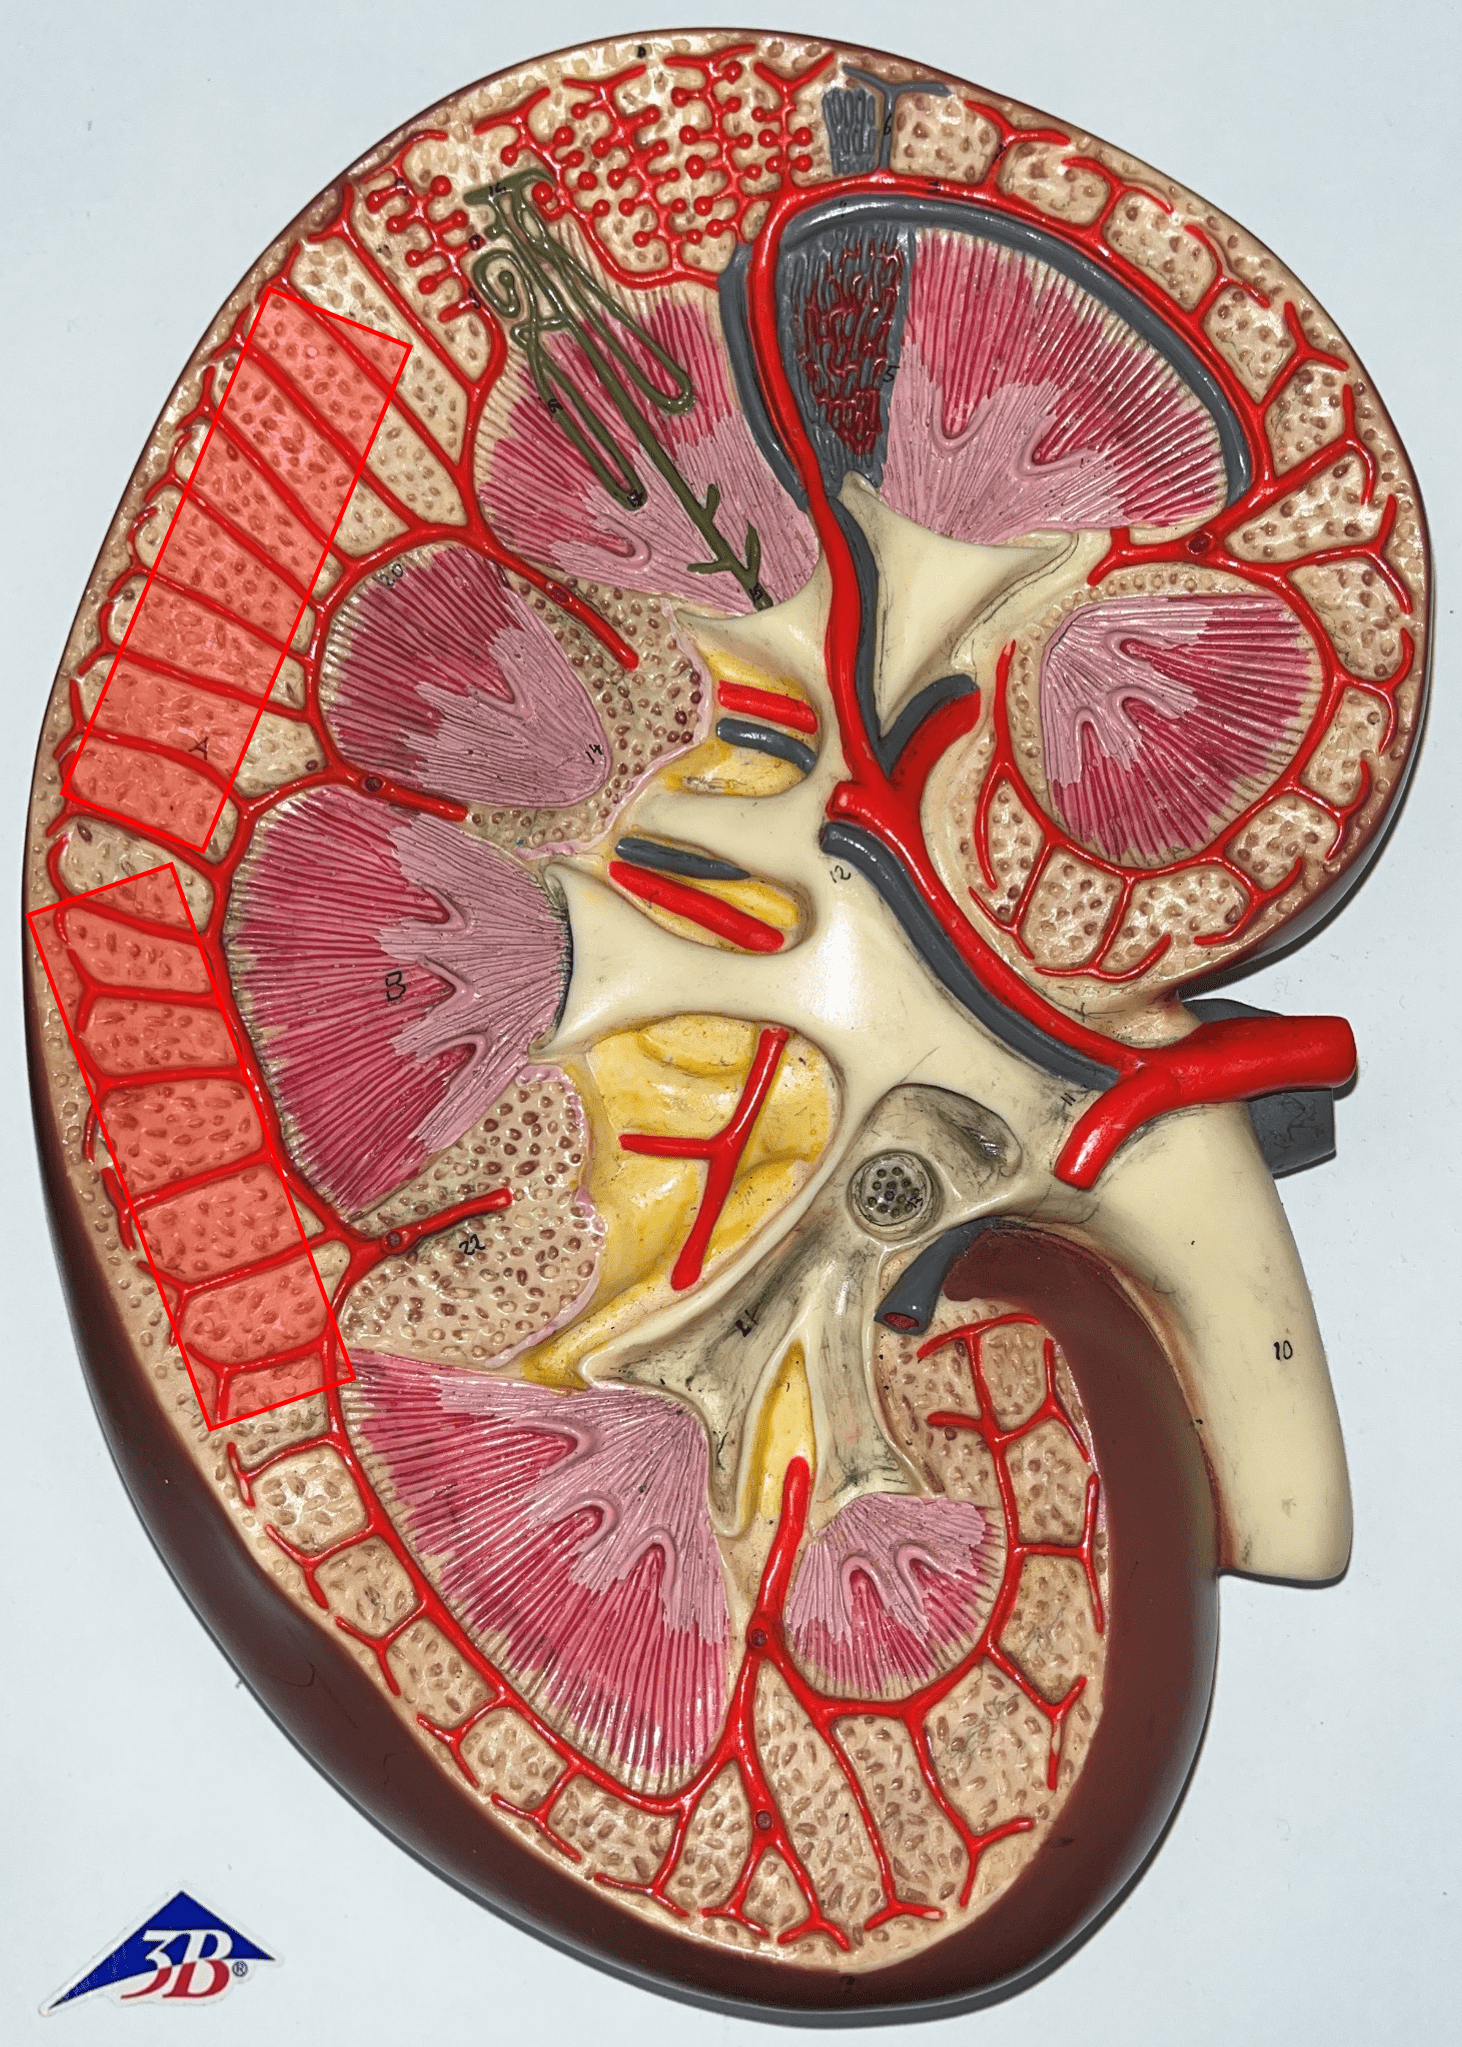

renal cortex

• The outermost region of the internal kidney.

• Superficial to the renal medulla.

• Appears slightly granular.

• Superficial to the renal medulla.

• Appears slightly granular.

interlobar artery

• Extends between the renal pyramids.

• Branches of a segmental a.

• Branches into smaller arcuate aa.

• Branches of a segmental a.

• Branches into smaller arcuate aa.

arcuate artery

• Extends along the base of the renal pyramids.

• Branches of an interlobar a.

• Branches into smaller interlobular aa.

• Branches of an interlobar a.

• Branches into smaller interlobular aa.

interlobular artery

• Extends through the renal cortex.

• Branches of an arcuate a.

• Branches into an afferent arteriole of a glomerulus.

• Branches of an arcuate a.

• Branches into an afferent arteriole of a glomerulus.